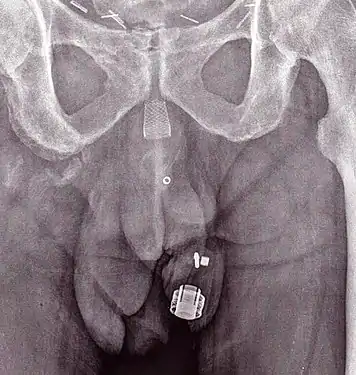

Artificial urinary sphincters (left to right: AMS 800 and ZSI 375)

Frederic Foley was the first to describe an externally worn artificial urinary sphincter to treat urinary incontinence, published in 1947.[5] In 1972, F. Brantley Scott and colleagues from Baylor College of Medicine designed the first precursor of contemporary artificial urinary sphincter.[6][7] The first AUS model on the market was the AMS 800 (Boston Scientific, Marlborough, MA), developed 50 years ago.[8][9] It is a 3-component device with a cuff placed around the urethra, a pump inserted in the scrotum and a pressure generating reservoir placed in the pelvis, which comes as a kit to prepare and to fill up before implantation.[10]

Another AUS model is the ZSI 375 (Zephyr Surgical Implants, Geneva, Switzerland), introduced in 2008.[11] It is a one-piece two-part device with a cuff and a pump unit with an integrated spring; it comes in one piece, pre-connected and pre-filled.[1][12] There is no abdominal component in the ZSI 375, which along with its ready-to-implant configuration reduces the operating time.[13] Furthermore, because there is no abdominal component, surgical interventions in the retroperitoneal space are not required. Previous surgeries, such as radical prostatectomy, may lead to post-operative scarring and fibrosis in the retroperitoneal space. Thus, avoiding dissection of retroperitoneal tissues avoids risks of surgical complications.[14][15] Another advantage of the ZSI 375 model is the possibility to increase or decrease the pressure inside the device after implantation to meet the desired continence rate and satisfaction of the patient. These adjustments particularly help to control continence in cases of post-implantation urethral atrophy or urinary retention (poor urine flow).[16][17][13] Adjustment of the pressure can be done in an outpatient setting by adding or removing sterile saline solution via a syringe through the scrotum.[12] By 2019, more than 4,500 ZSI 375 artificial urinary sphincters have been implanted worldwide.[11]

In both models sterile saline solution inside the system is used to generate pressure and compress the urethra (to prevent urine from leaking). The urethral cuff is deflated manually by pressing the control pump that is placed in the scrotum, allowing the patient to empty the bladder. The urethral cuff then re-inflates automatically to refill the urethral cuff and once again prevent urine from leaking.[1][18]